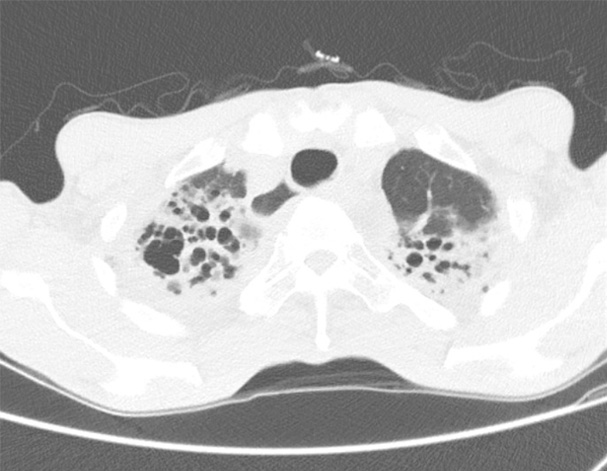

비결핵항산균에 감염된 폐사진

비결핵항산균에 감염된 환자를 한약으로 다스리는 증례논문(일본)

*기관지확장증에서 비결핵항산균 관리는 중요합니다.

A 72-year-old male was referred to our hospital in August 2001 for his pulmonary M. fortuitum infection. His symptoms were coughing, pyrexia, hemoptysis, general malaise, and insomnia. He had been suffering from these symptoms since 1982, though the intensive anti-mycobacterial chemotherapy such as three-drug (RFP, SM, and INH), twice two-drug (KM and SM and cycloserine and enviomycin) and four-drug (CAM, EB, RFP, and KM) regimens were administered for 26 months from July 1999. His symptoms tentatively improved after chemotherapy, but soon recurred with smear positive sputum. We decided to withdraw all antibacterial agents to treat him with decoction of Ninjinyoueito according to the diagnostics Kampo medical science in September 2001. After this prescription, his subjective symptoms gradually improved, and ten months later his sputum converted to smear negative. Because of recurrence of his general malaise in August 2002, we replaced the Ninjinyoueito by Seishoekkito, based on the Kampo diagnostics. His physical conditions remained good until 2005. In addition, the sputum smear examination maintain the level below +/-. We evaluate that Kampo (Chinese traditional medicine) treatment resulted in favorable response. Though it is not common to prescribe Kampo-medicine for intractable infectious diseases, we believe that Kampo-medicine is effective in some cases associated with host defense mechanisms.

일본에 있는 병원에서 비결핵항산균 환자의 치료 사례 논문입니다. 요지는 다음과 같습니다.

"양약치료 후 일시 호전 되었으나 계속 양성반응이 나타났음. 이후 한약치료로 바꾸기로 하고 처방함. 한약 치료 후 환자의 주관 증상이 호전되고 가래검사에서도 음성으로 호전되었다"